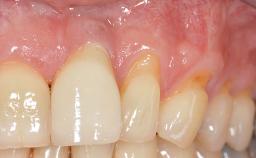

Implant Placement in the Esthetic Zone and Coverage of Multiple Gingival Recessions

This case illustrates use of a modified ‘tunnel’ technique, which has been shown to be highly effective in root coverage procedures. The tunnel technique is used to achieve soft-tissue augmentation across the anterior area, including the planned implant site, using collagen matrix as grafting material. The patient is a 47-year-old woman with high esthetic expectations. Her main concern was the appearance of the anterior teeth and their “elongation”.

Soft Tissue Grafting Staged